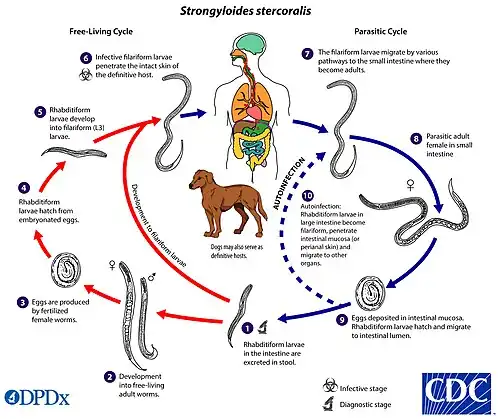

Strongyloidiasis is a human parasitic disease caused by the nematode called Strongyloides stercoralis, or sometimes the closely related S. fülleborni. These helminths belong to a group of nematodes called roundworms. These intestinal worms can cause a number of symptoms in people, principally skin symptoms, abdominal pain, diarrhea and weight loss, but also many other specific and vague symptoms in disseminated disease, and severe life-threatening conditions through hyperinfection. In some people, particularly those who require corticosteroids or other immunosuppressive medication, Strongyloides can cause a hyperinfection syndrome that can lead to death if untreated. The diagnosis is made by blood and stool tests. The medication ivermectin is widely used to treat strongyloidiasis.

Strongyloides infection occurs in five forms. As the infection continues and the larvae mature, there may be respiratory symptoms (Löffler's syndrome). The infection may then become chronic with mainly digestive symptoms. There may be respiratory, skin, and digestive symptoms of reinfection (when larvae migrate through the body) from the skin to the lungs and finally to the small intestine. Finally, the hyperinfection syndrome causes symptoms in many organ systems, including the central nervous system.[4][5]

Diagnosis rests on the microscopic identification of larvae (rhabditiform and occasionally filariform) in the stool or duodenal fluid. Examination of many samples may be necessary, and not always sufficient, because direct stool examination is relatively insensitive, with a single sample only able to detect larvae in about 25% of cases.[14] It can take 4 weeks from initial infection to the passage of larvae in the stool.